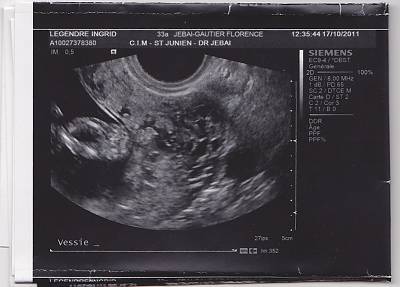

besoin d aide qui si connait en echo fille ou garcon

bonjour j au rais souhaiter savoir si vous connaissez en echo pouvez vous me donner votre avis merci fille ou garcon

posté par ingrid1523 le 24-11-2011 à 08:15

je vous mets une autre